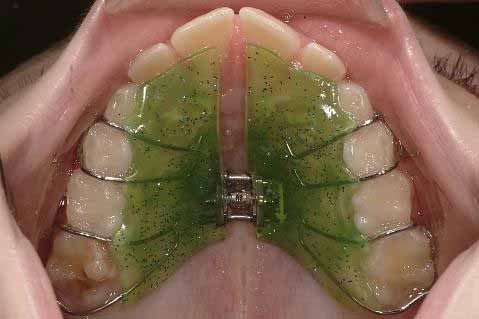

混合歯列期または後期の乳歯列期における片側性交叉咬合の治療は、通常、クワドヘリックス(画像2)または拡張床(画像3)を用いて行われます。

- クワドヘリックスは、拡張床よりも優れた、非常に効果的な治療法です。

- クワドヘリックスまたは拡張床のいずれかを使用した交叉咬合治療が成功すれば、同等の長期安定性が期待でき、予後は非常に良好です。

- クワドヘリックスは、拡大床よりも費用対効果に優れています。

- クワドヘリックスは、直接および間接的な費用が少なく、治療のやり直しを必要とする治療ミスも少ないです。